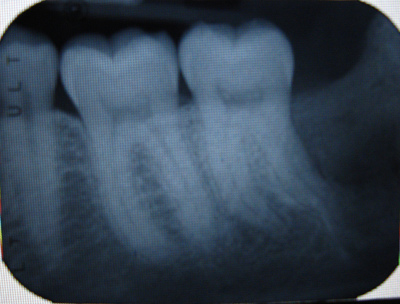

- Обследование — собирается вся необходимая информация: доктор обследует ткань, назначает рентген и томографию челюсти, сдаётся анализ крови. Длительность всех процедур не более двух дней.